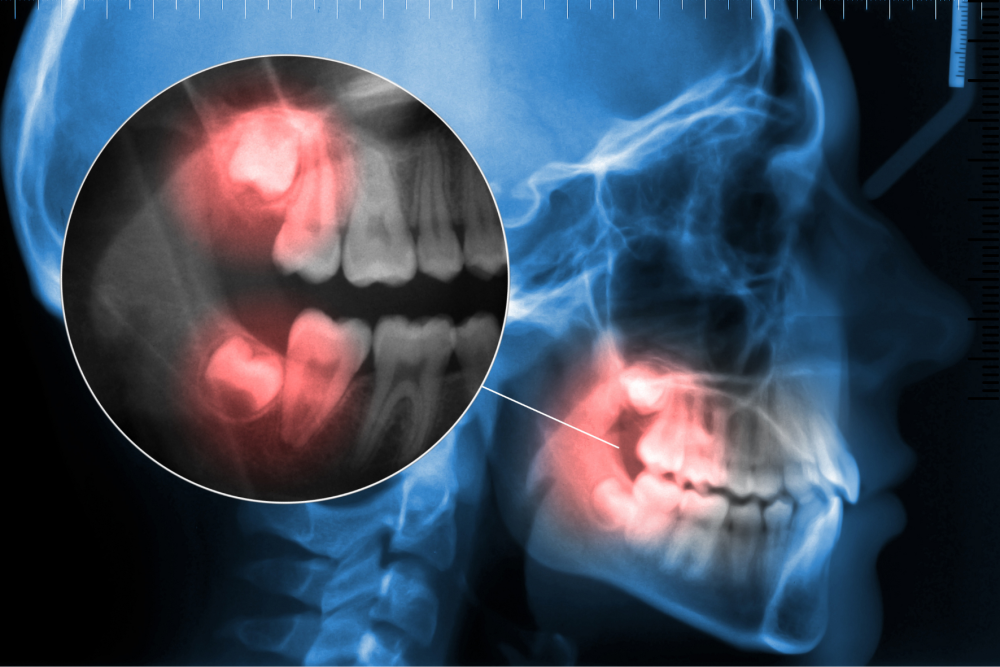

Zęby mądrości (ósemki) to ostatnie zęby trzonowe po obu stronach szczęki i żuchwy . Pojawiają się one lub rosną jako ostatnie, zwykle w wieku od 16 do 20 roku życia. Ze względu na to, że zęby mądrości (ósemki) są ostatnimi pojawiającymi się zębami stałymi, często w jamie ustnej pozostaje na nie zbyt mało miejsca. Może to prowadzić do zatrzymania ósemek (zębów mądrości). Gdy ząb jest niewidoczny w jamie ustnej i ze wszystkich stron jest otoczony kością mówi się o zatrzymaniu całkowitym. Taki ząb może być przyczyną obrzęku i bólu.

Przed umówieniem się na zabieg chirurgicznego usunięcia ( ekstracji) ósemki (zęba mądrości), konieczne jest zrobienia zdjęcia panoramicznego RTG i badania tomograficznego, aby umożliwić lekarzowi ocenę położenia zęba ,co jest warunkiem bezpiecznego przeprowadzenia zabiegu.